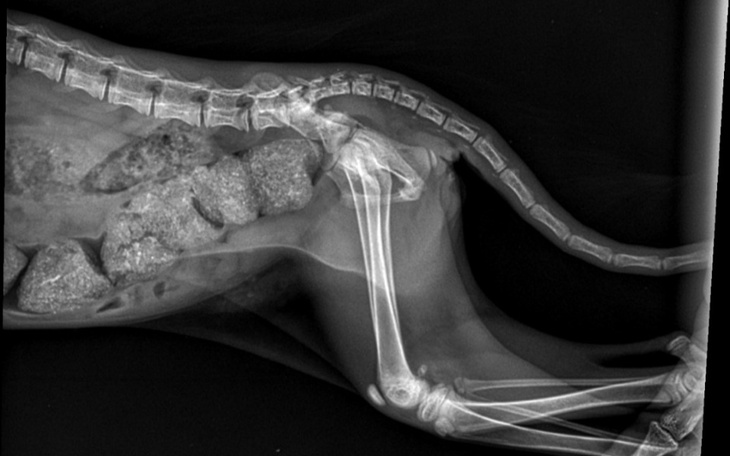

To małe kocie dziecko zostało najechane przez samochód gdy w strachu schowało swoje drobne ciałko przed widokiem ludzi. Niestety nie jest dobrze. Maleństwo czeka operacja i to bardzo kosztowna. Obecnie przebywa w komu tymczasowym, jest kenelowana, ponieważ nie może się ruszać i bardzo cierpi. Nie tak powinno wyglądać kocie dzieciństwo, oj nie tak... Zbiórka powstała w celu zebrania funduszy na zabieg i utrzymanie koteczki do momentu znalezienia jej odpowiedzialnego domu, takiego który będzie ją kochał i dbał do końca jej kocich dni.